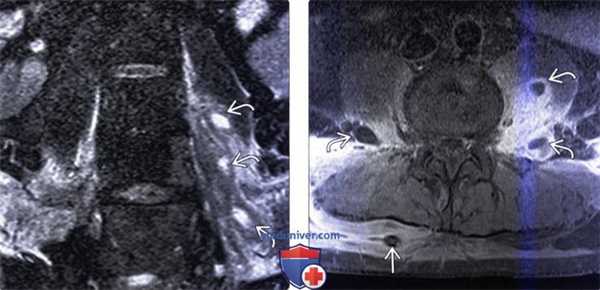

(Слева) Аксиальный срез, Т1-ВИ: аморфное низкоинтенсивное образование в области тела шейного позвонка и вентральной поверхности длинных мышц шеи. Паравертебральная флегмона стала следствием спондилодисцита.

(Справа) Аксиальный срез, Т2-ВИ: гетерогенное жидкостное образование в толще правой поясничной мышцы. Оно окружено толстой неправильной формы гипоинтенсивной стенкой, центральная часть отличается гиперинтенсивностью сигнала. Правая поясничная мышца с признаками диффузного усиления сигнала вследствие отека.

(Слева) Аксиальный срез, Т1-ВИ FS с КУ: ярко контрастирующееся гетерогенное паравертебральное жидкостное образование, окружающее переднюю и боковые поверхности тела поясничного позвонка. Накапливающие контраст ткани располагаются в непосредственной близости к аорте.

(Справа) Фронтальный КТ-срез: справа определяется паравертебральный абсцесс, сформировавшийся на фоне спондилодисцита. В полости абсцесса виден катетер. Гиперденсное внутреннее содержимое абсцесса может представлять собой продукты распада крови и гной.

(Слева) Фронтальный срез, STIR МР-И: в толще отечной левой поясничной мышцы видны множественные гиперинтенсивные жид костные скопления. Эти паравертебральные абсцессы скорее всего гематогенного происхождения (пациент являлся внутривенным наркоманом). STIR-режим наиболее информативен в отношении раннего выявления паравертебральных очагов воспаления.

(Справа) Аксиальный срез, Т1-ВИ, FS с КУ: множественные небольшие контрастирующиеся по периферии и гипоинтенсивные в центре жидкостные образования в толще обеих поясничных мышц. Поверхностные абсцессы были дренированы чрескожно со стороны спины.